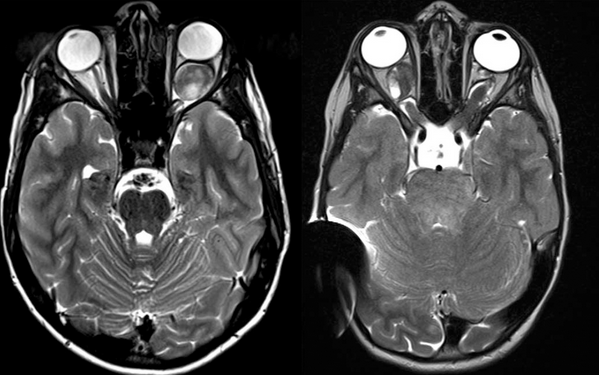

视神经胶质瘤是影响儿童和青少年皮质前视觉通路的低度肿瘤。它们会影响视神经,视交叉,视束和放射线,可能是散发性的,也可能与一类神经纤维瘤病相关。分离到视神经神经胶质瘤(ONG)是视神经胶质瘤的一个亚组,其治疗仍有争议。近年来,ONG治疗出现了新的发展。

大多数视神经胶质瘤存在某种形式的视觉症状,这些症状由肿瘤的位置决定。视力丧失是一种常见的症状,涉及一只眼睛或两只眼睛。通常,仅一部分视野会受到影响。其他视觉症状包括眼球突出(眼球突出),眼球震颤(弹性眼)或斜视(眼球漂移)。涉及下丘脑的肿瘤可导致肥胖,性早熟或其他激素功能障碍。延伸到三脑室的肿瘤会由于脑脊液流动的阻塞而导致脑积水,从而导致颅压升高的症状(头痛,呕吐,平衡困难,嗜睡)。

NF1患者的视神经胶质瘤发病率很高(15-20%),但是这些视神经胶质瘤的病程很缓慢,一般不会引起视觉障碍。NF1患者应每年接受眼科检查,如果发现视力障碍,建议使用MRI评估视神经胶质瘤。除非肿瘤引起视力障碍或其他神经系统症状,否则不建议对患有NF1的患者的视神经胶质瘤进行治疗。